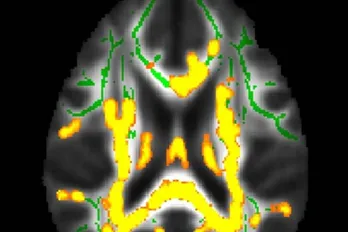

Xét nghiệm máu giúp phát hiện bệnh Alzheimer chính xác hơn các bác sỹ có kinh nghiệm. (Nguồn: Neuroscience News)